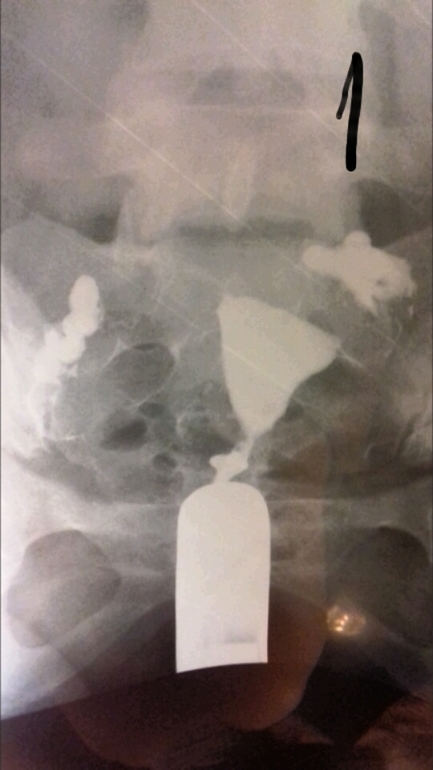

ГСГ помогите расшифровать.

ГСГ, ЭХО, МСГ, ФертилоскопияВсем привет. Кто понимает в снимках. Сделала гсг. На третьем сказали жидкость вышла, но как-то долго она выходила и спайки видно, поставили эндометриоз и спаечный процесс в брюшной полости. Беременность не наступает и стимуляции были. В 2006 году было кесарево и в 2012 прижигали эррозию ш/м, больше ничего.